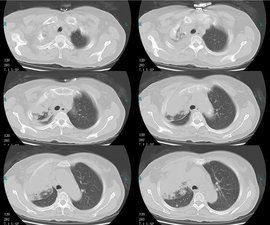

CT表現

中央型肺癌①腫瘤沿支氣管壁生長,顯示支氣管壁不規則增厚和管腔狹窄,甚至造成支氣管閉塞。

②腫瘤致支氣管狹窄而發生阻塞性氣腫、阻塞性肺炎,甚至發生肺膿腫。

③腫瘤形成較大肺門腫塊,此時多合併肺不張,腫塊與不張肺相連,形成“S”狀或反“S”狀邊緣。

④中央型肺癌可直接侵犯縱隔,表現為與肺門腫瘤相連的縱隔腫塊,增強檢查不但有助於鑑別肺門腫塊與血管,且可顯示肺門及與之相連的縱隔腫塊呈同樣程度強化。